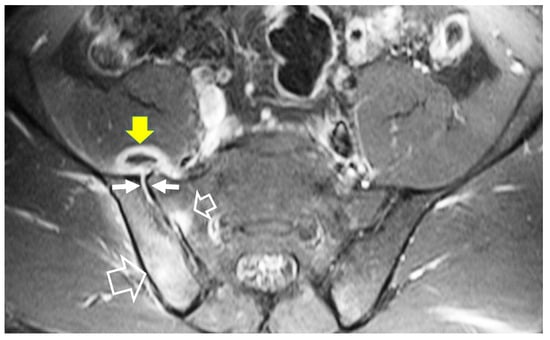

- Bozgeyik, Z.; Ozdemir, H.; Demirdag, K.; Ozden, M.; Sonmezgoz, F.; Ozgocmen, S. Clinical and MRI findings of brucellar spondylodiscitis. Eur. J. Radiol. 2008, 67, 153–158. [Google Scholar] [CrossRef]

- Bozgeyik, Z.; Aglamis, S.; Bozdag, P.G.; Denk, A. Magnetic resonance imaging findings of musculoskeletal brucellosis. Clin. Imaging 2014, 38, 719–723. [Google Scholar] [CrossRef]

- Ozaksoy, D.; Yucesoy, K.; Yucesoy, M.; Kovanlikaya, I.; Yuce, A.; Naderi, S. Brucellar spondylitis: MRI findings. Eur. Spine J. 2001, 10, 529–533. [Google Scholar] [CrossRef] [PubMed]

- Harman, M.; Unal, O.; Onbasi, K.T.; Kiymaz, N.; Arslan, H. Brucellar spondylodiscitis: MRI diagnosis. Clin. Imaging 2001, 25, 421–427. [Google Scholar] [CrossRef] [PubMed]

- Chelli Bouaziz, M.; Ladeb, M.F.; Chakroun, M.; Chaabane, S. Spinal brucellosis: A review. Skelet. Radiol. 2008, 37, 785–790. [Google Scholar] [CrossRef]

- Raptopoulou, A.; Karantanas, A.H.; Poumboulidis, K.; Grollios, G.; Raptopoulou-Gigi, M.; Garyfallos, A. Brucellar spondylodiscitis: Noncontiguous multifocal involvement of the cervical, thoracic, and lumbar spine. Clin. Imaging 2006, 30, 214–217. [Google Scholar] [CrossRef] [PubMed]

- Sharif, H.S.; Clark, D.C.; Aabed, M.Y.; Haddad, M.C.; al Deeb, S.M.; Yaqub, B.; al Moutaery, K.R. Granulomatous spinal infections: MR imaging. Radiology 1990, 177, 101–107. [Google Scholar] [CrossRef]

- al-Shahed, M.S.; Sharif, H.S.; Haddad, M.C.; Aabed, M.Y.; Sammak, B.M.; Mutairi, M.A. Imaging features of musculoskeletal brucellosis. Radiographics 1994, 14, 333–348. [Google Scholar] [CrossRef]

- Guo, H.; Lan, S.; He, Y.; Tiheiran, M.; Liu, W. Differentiating brucella spondylitis from tuberculous spondylitis by the conventional MRI and MR T2 mapping: A prospective study. Eur. J. Med. Res. 2021, 26, 125. [Google Scholar] [CrossRef]

- Li, W.; Zhao, Y.H.; Liu, J.; Duan, Y.W.; Gao, M.; Lu, Y.T.; Yao, L.; Li, S.L. Imaging diagnosis of brucella spondylitis and tuberculous spondylitis. Zhonghua Yi Xue Za Zhi 2018, 98, 2341–2345. [Google Scholar] [CrossRef]